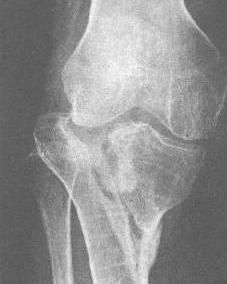

胫骨平台是位于胫骨上端的一个平台,与股骨的髁部形成膝关节。胫骨平台骨折是指胫骨平台部位发生的骨折,可能是由于直接撞击、跌倒或扭伤等原因引起。根据骨折的严重程度和位置,可分为多种类型,如单纯骨折、粉碎性骨折等。